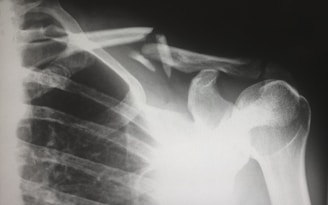

Snap, snap, crackle, pop. That was the sound of my life changing in an instant during a summer stroll. I fell on slightly uneven pavement and broke three bones in my ankle and severely dislocated it, leading to a surgery and months of recovery.

An orthopedic injury is typically a traumatic event. The recovery can elicit many emotions. As a psychotherapist, I found that not much has been written on coping with the psychological impact of such an injury and the recovery that follows.